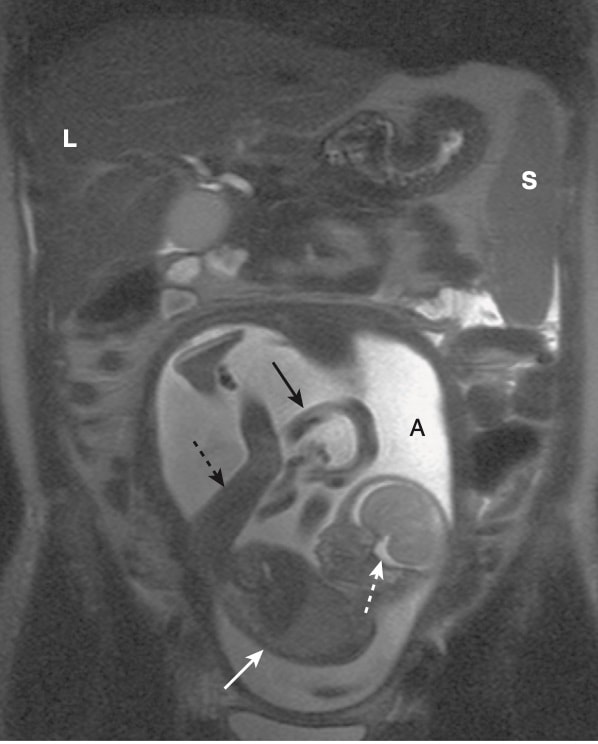

- Tuy nhiên, Hiệp hội Hình ảnh học Hoa kỳ (American College of Radiology) tuyên bố rằng bệnh nhân mang thai có thể được chụp MRI ở bất kỳ giai đoạn nào của thai kỳ nếu quyết định rằng tỷ lệ rủi ro / lợi ích của bệnh nhân có lợi cho việc thực hiện (Hình 12).